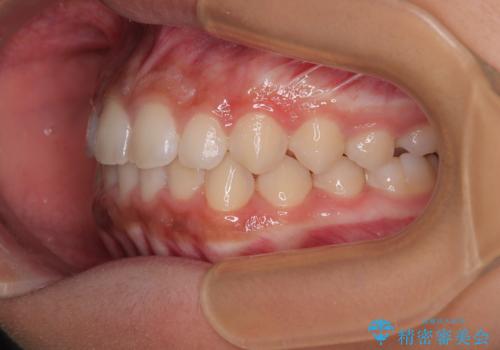

気になるすきっ歯を短期間で改善 インビザライン矯正

- 前歯の隙間を気にして来院された患者様です。

口元の突出感があり、小臼歯4本を抜歯して口元を引っ込める矯正治療も提案しましたが、本人は口元の突出感は気になっていないとのことで、インビザラインにて隙間やデコボコを改善することとしました。

軽度の歯列不正であったため、廉価版のインビザライン・モデレートパッケージにて治療を終えることができました。